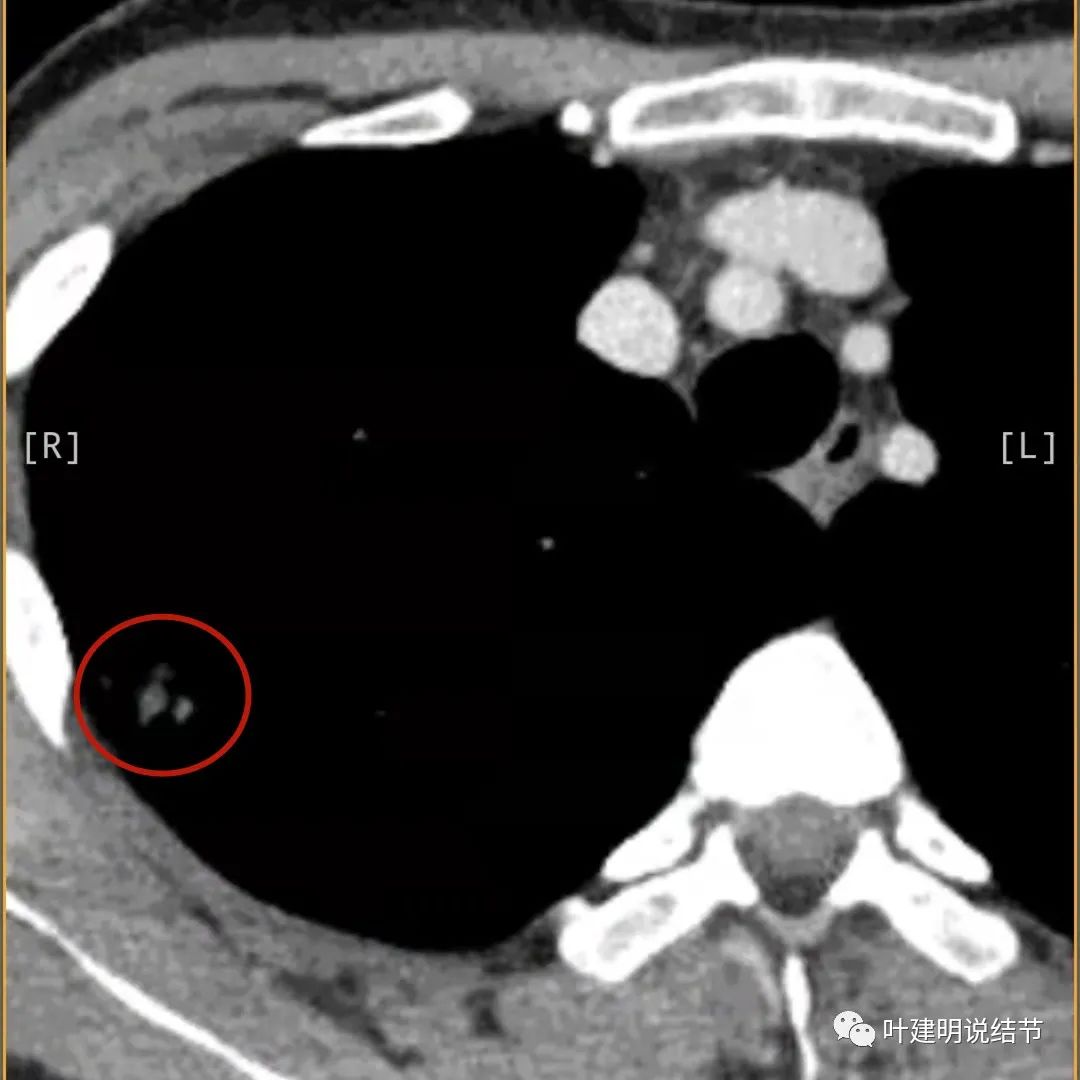

有卫星病灶(绿色箭头)

胸壁侧病灶较厚,模糊(蓝色箭头),仍见卫星灶(绿色箭头)